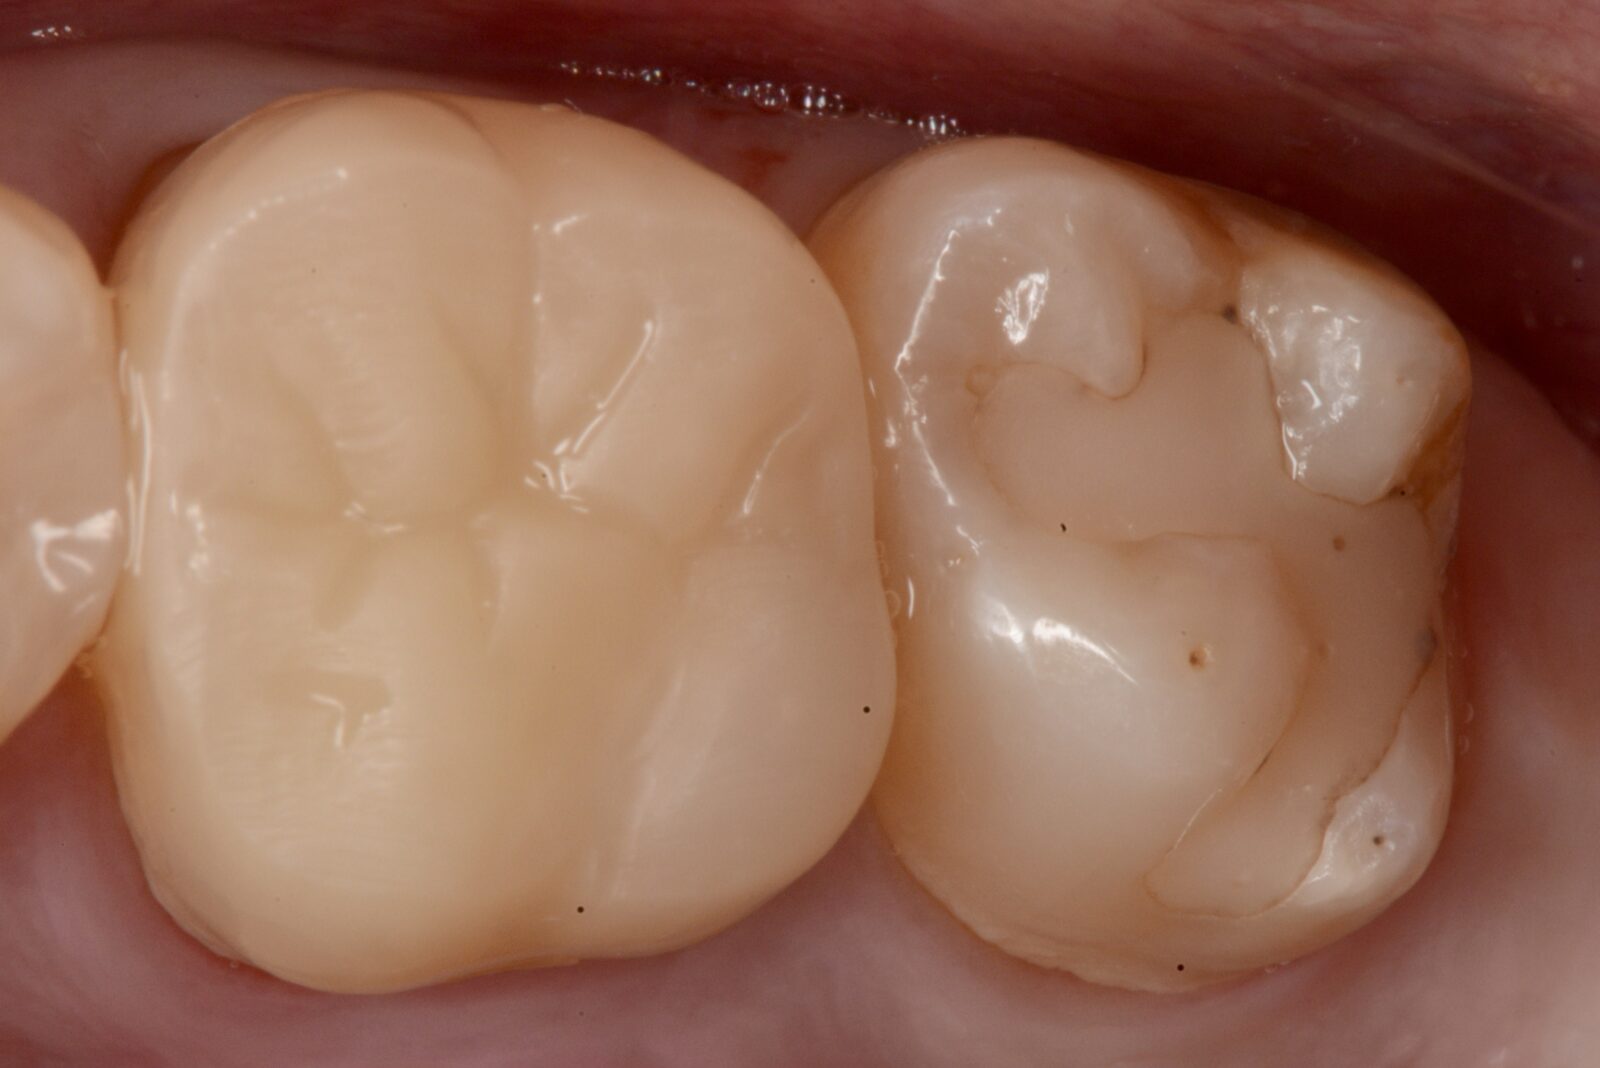

治療前 治療後

右下7ダイレクトボンディング

虫歯の治療希望で、右下の旧充填物と感染歯質の除去。 ラバーダム下で、プラークアウトと歯面処理を行い、接着操作とレジン充填を行った。 咬合調整はほぼなく研磨で終了。